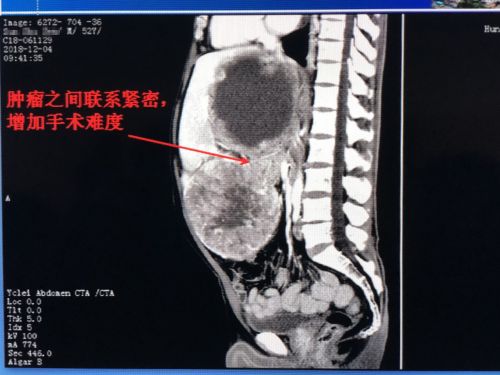

肿瘤与肿瘤之间粘连紧密,手术难度大。

进一步检查发现,陈伟雄右肝有一个24厘米的囊性肿块,左肝一个20厘米的实性肿块,下腹部还有一个5cm的实性肿块。首席专家吴金术教授率彭创、易为民、郭超等组成的专家团队充分评估手术风险,精心制定完善的手术计划后,于12月13日为患者施行手术。

术中发现,右肝巨大囊性肿瘤基本占据整个腹腔,且坏死出血。在切除腹壁小肿块和左肝外叶巨大肿瘤腾出空间后,将右肝囊性肿瘤内的陈旧性出血抽出2500毫升。这时,右肝肿瘤明显缩小,再进行前入路解剖性右半肝切除。采取分组手术完整切除肿瘤,三个肿瘤共计7.13公斤,其中左肝实质肿块约20×18×13cm大小,右肝囊性肿块24×20×17cm大小,犹如一对“双胞胎”。